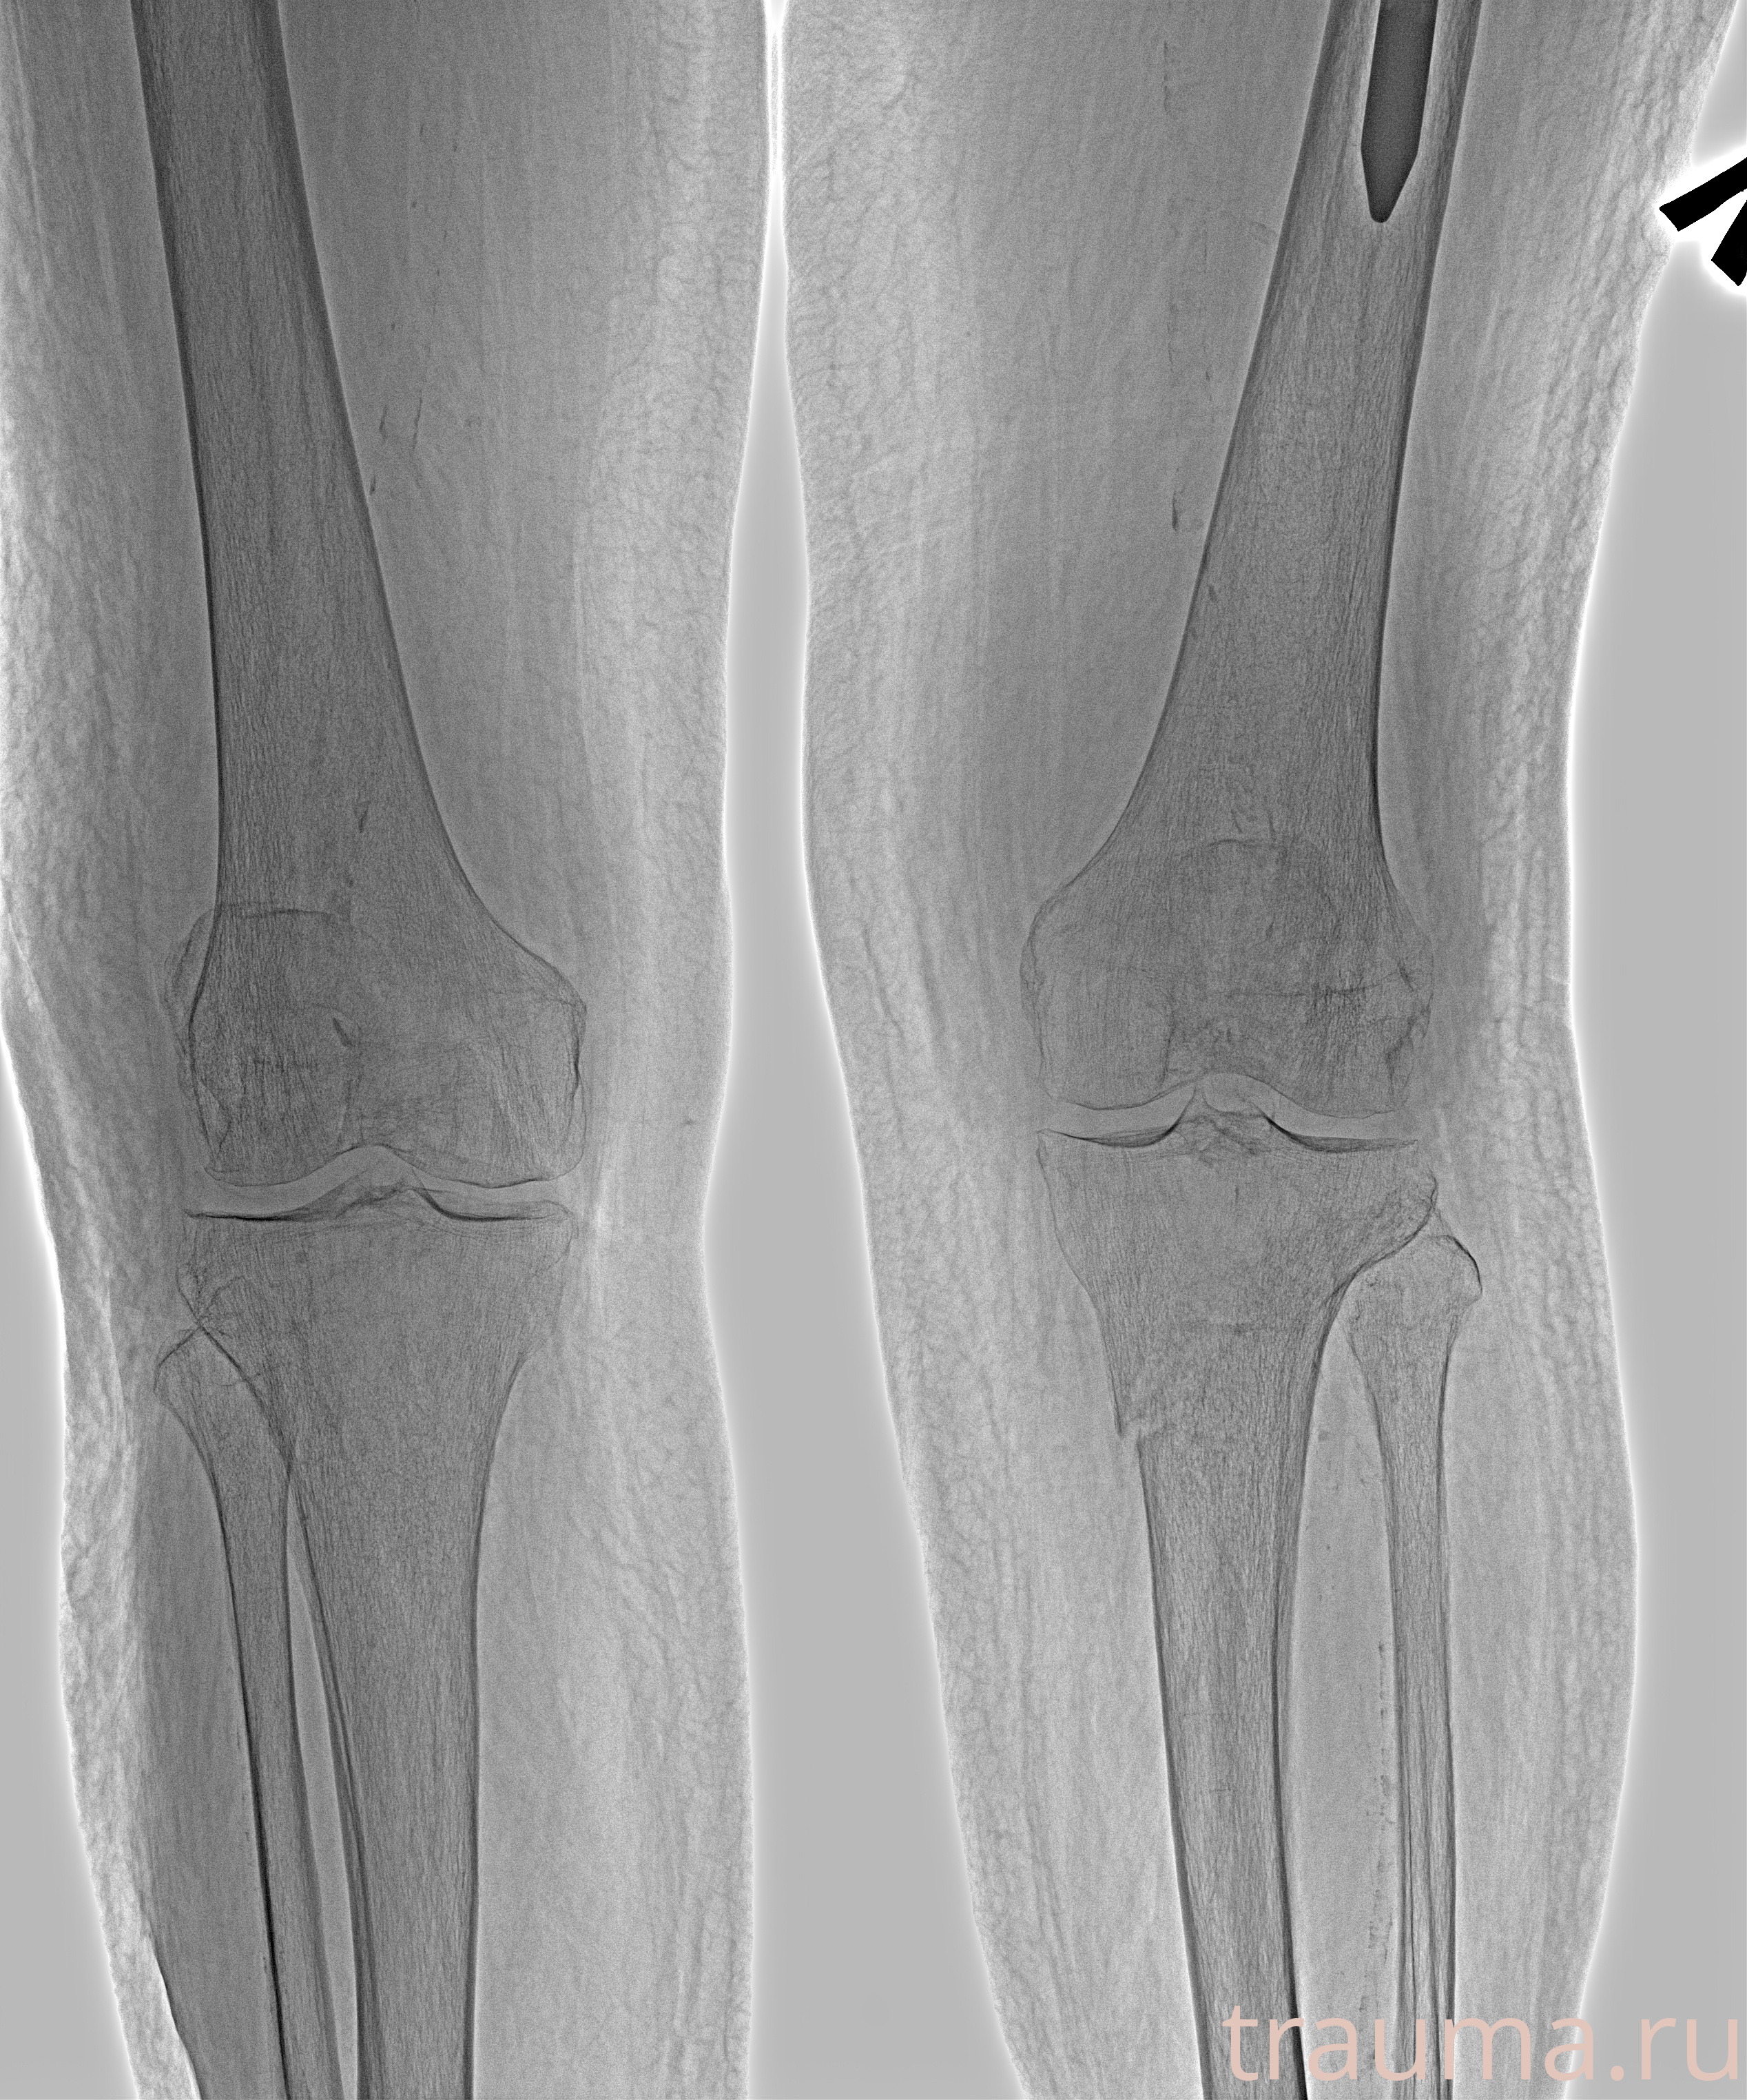

Рентген на дому: по вашему адресу приезжает врач-рентгенолог, травматолог-ортопед с мобильным рентгеновским аппаратом, проводит диагностику травмы или заболевания, делает необходимые рентгенограммы, дает рекомендации по дальнейшему лечению. Получить качественные снимки в домашних условиях возможно благодаря уникальной методике, разработанной МосРентген Центром для института  Склифосовского